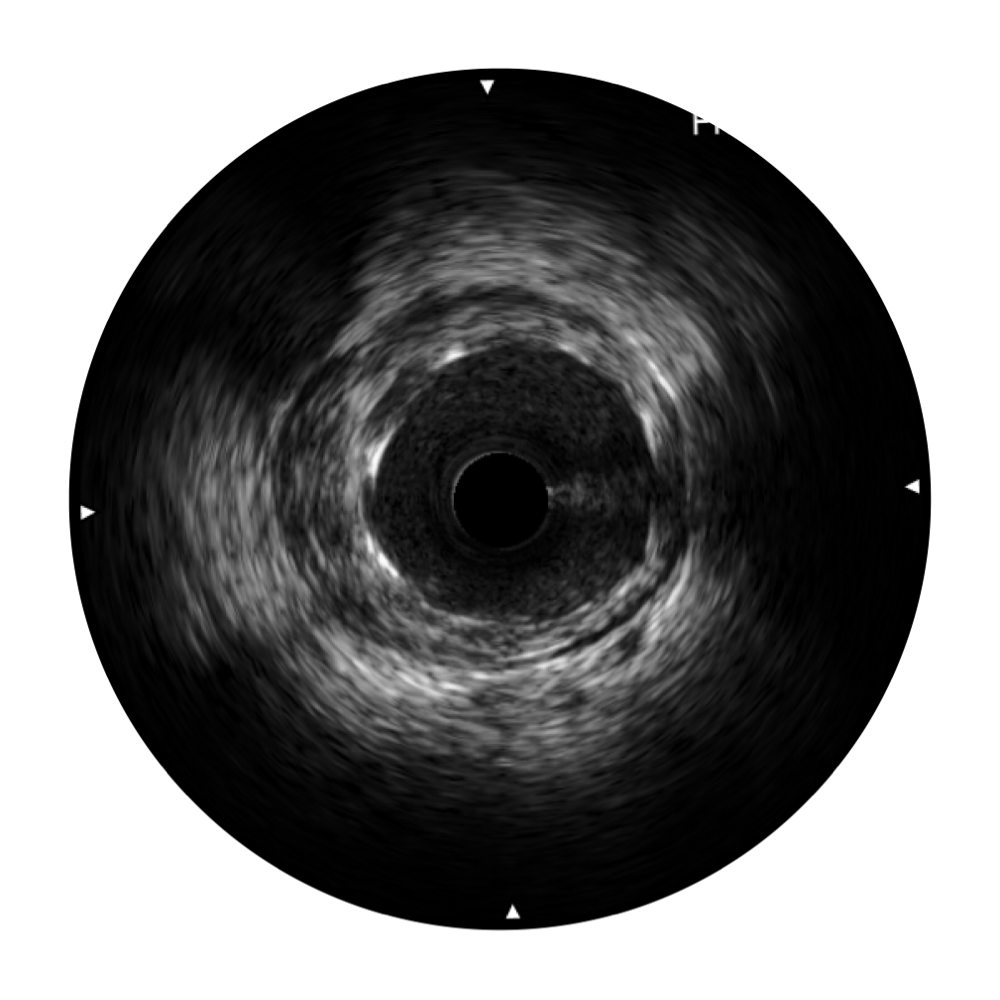

血管内超声(IVUS) 通过对病变程度、性质和累及范围的精确判断,可帮助选择治疗策略和方法,指导介入治疗过程,能够降低主要不良心血管事件,改善预后,在复杂病变介入治疗中用于指导支架置入的优势更为明显。血管内超声(IVUS)已成为精准心血管介入治疗的“金标准”。

MILE米乐集团官网始终关注未满足的临床需求:超宽频成像技术同时提供高清分辨力和充足穿透深度,适应不同血管结构的治疗引导;智慧赋能,简化操作,降低临床应用难度和缩短学习曲线。

MILE米乐集团官网超宽频成像技术覆盖20-80MHz1或20-90MHz2频率范围, 提供优异的分辨力同时也保证充足的穿透深度